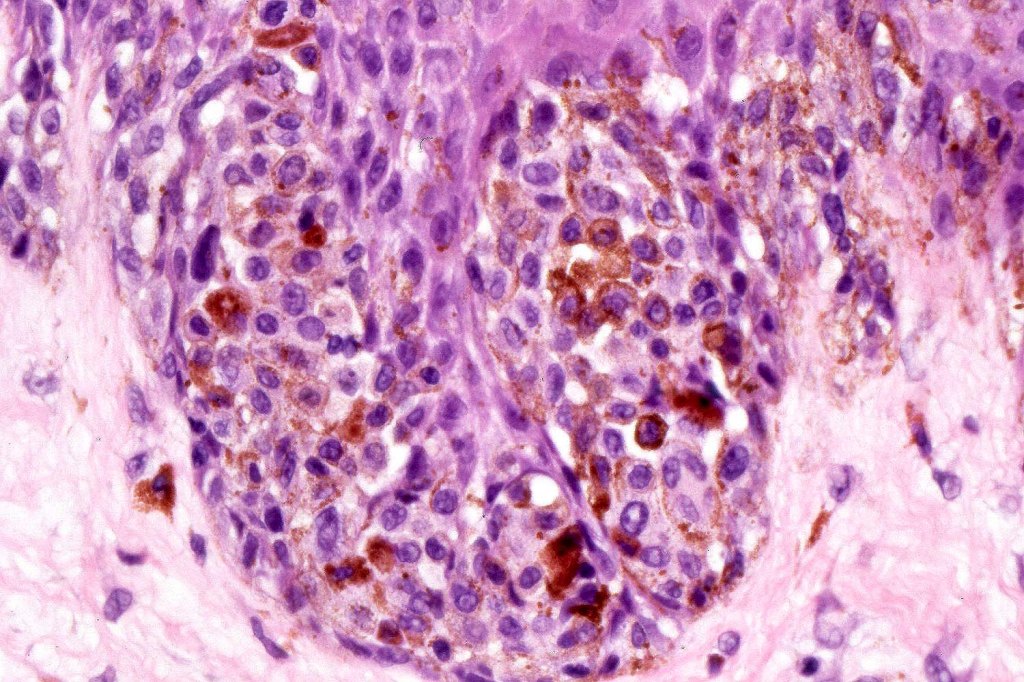

•Large dyscohesive nests with retraction artifact, not restricted to the tips of the epidermal ridges

•Heavy pigmentation (sometimes gray/green)

•Bridging common, often over multiple rete ridges

•Variable atypia (can be marked)

•Superficial dermal atypia

•Dermal fibrosis (sometimes lamellar)